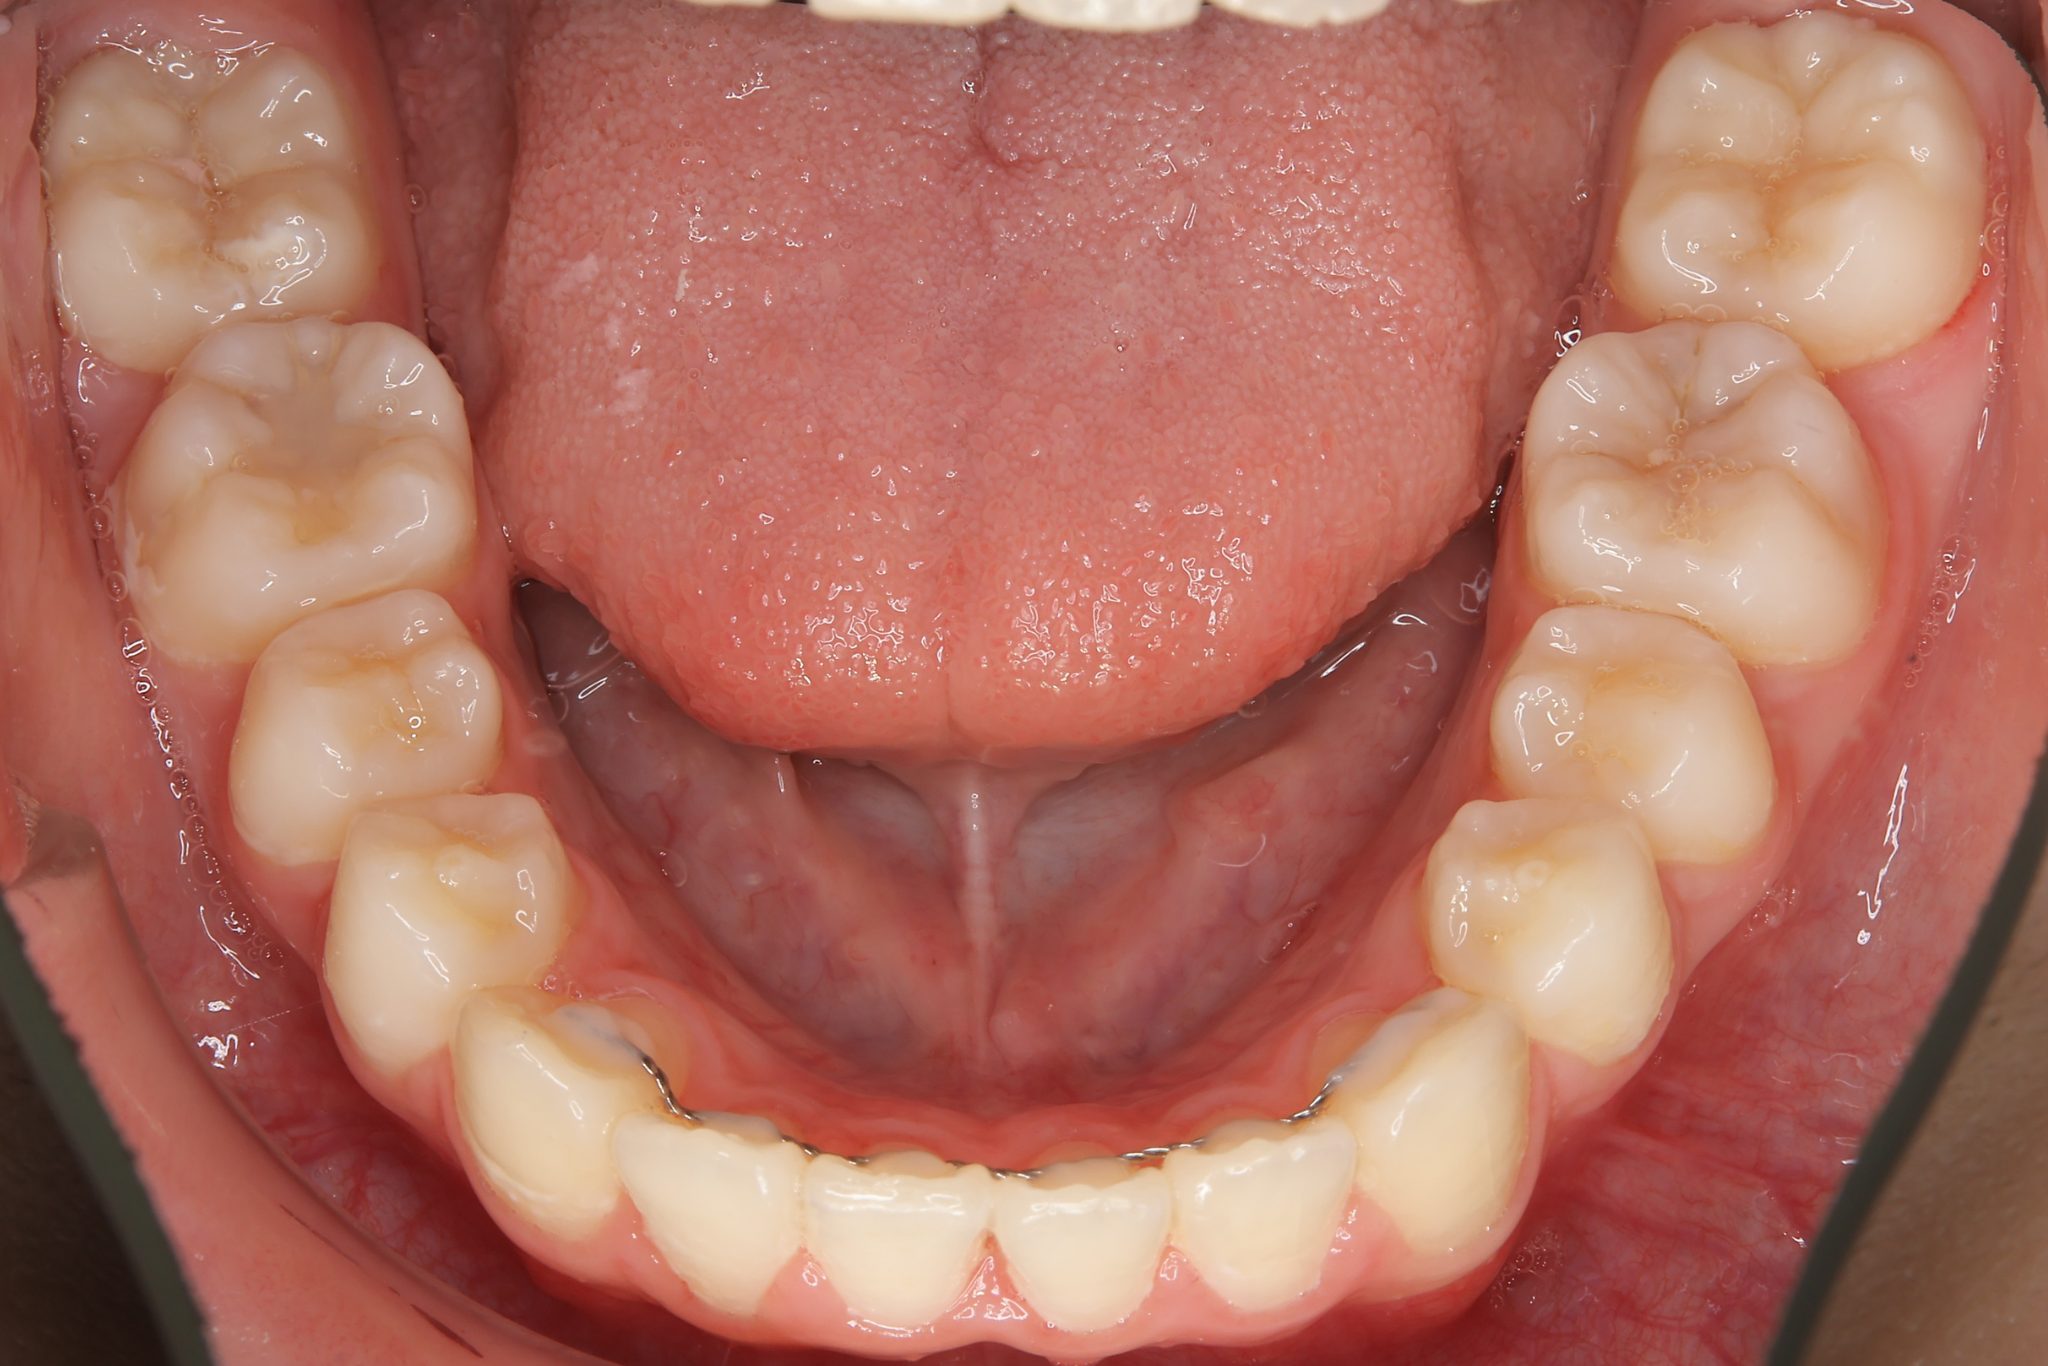

アフター

ワイヤー矯正治療|症例_1324

施術内容 MSEと下顎リンガルアーチを用いて上下顎骨を拡大した。

その後マルチブラケット装置を用いて非抜歯で歯牙を配列し、良好な咬合を獲得した。

治癒期間 1年5か月間